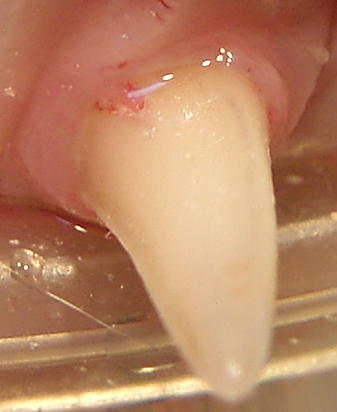

This is a painful dental resorptive lesion in a cat’s upper canine tooth.

Resorptive lesions: Although these can be seen in the dog, they are much more prevalent in the cat population. Most studies agree that on average, about 50% of domestic cats have at least one resorptive lesion.

Due to the destruction of the protective enamel that covers the surface of the tooth, these lesions can be very sensitive to those affected. Several theories have been proposed for the cause of these lesions, but to date, none has been proven. We do believe the incidence has increased over the past 100 years. Unless caught early, most of the teeth affected by resorptive lesions are best extracted.

Very early lesions may benefit from glass ionomer restoration, but in most cases, the restorations are lost and the lesion progresses within 18 months.